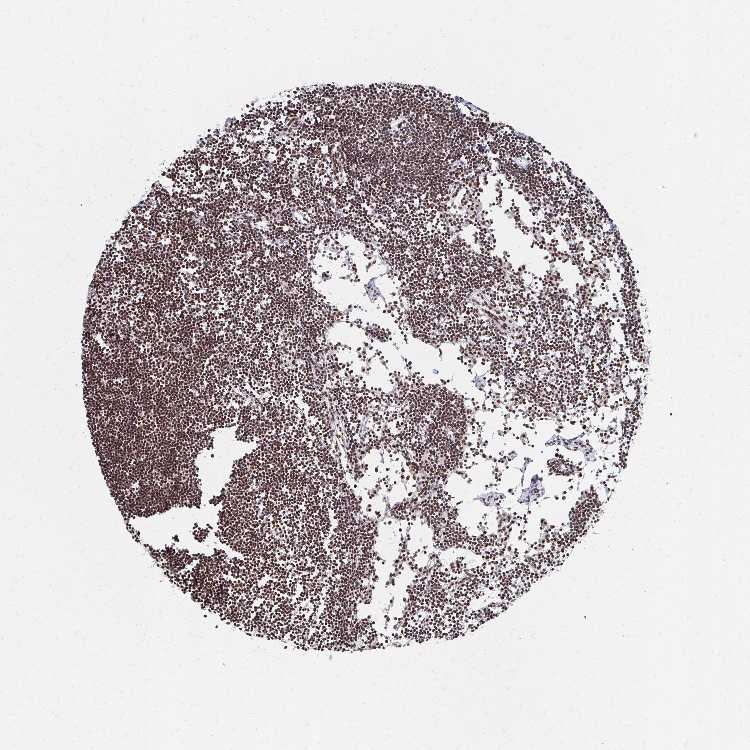

LYMPH NODE - Antibody stainingi

Antibody staining in the annotated cell types in the current human tissue is reported as not detected, low, medium, or high, based on conventional immunohistochemistry profiling in selected tissues. This score is based on the combination of the staining intensity and fraction of stained cells.

Each image is clickable and will lead to virtual microscopy that enables deeper exploration of all samples and also displays staining intensity scores, fraction scores and subcellular localization as well as patient and tissue information for each sample.

Antibody HPA049651

Germinal center cells High

Non-germinal center cells High